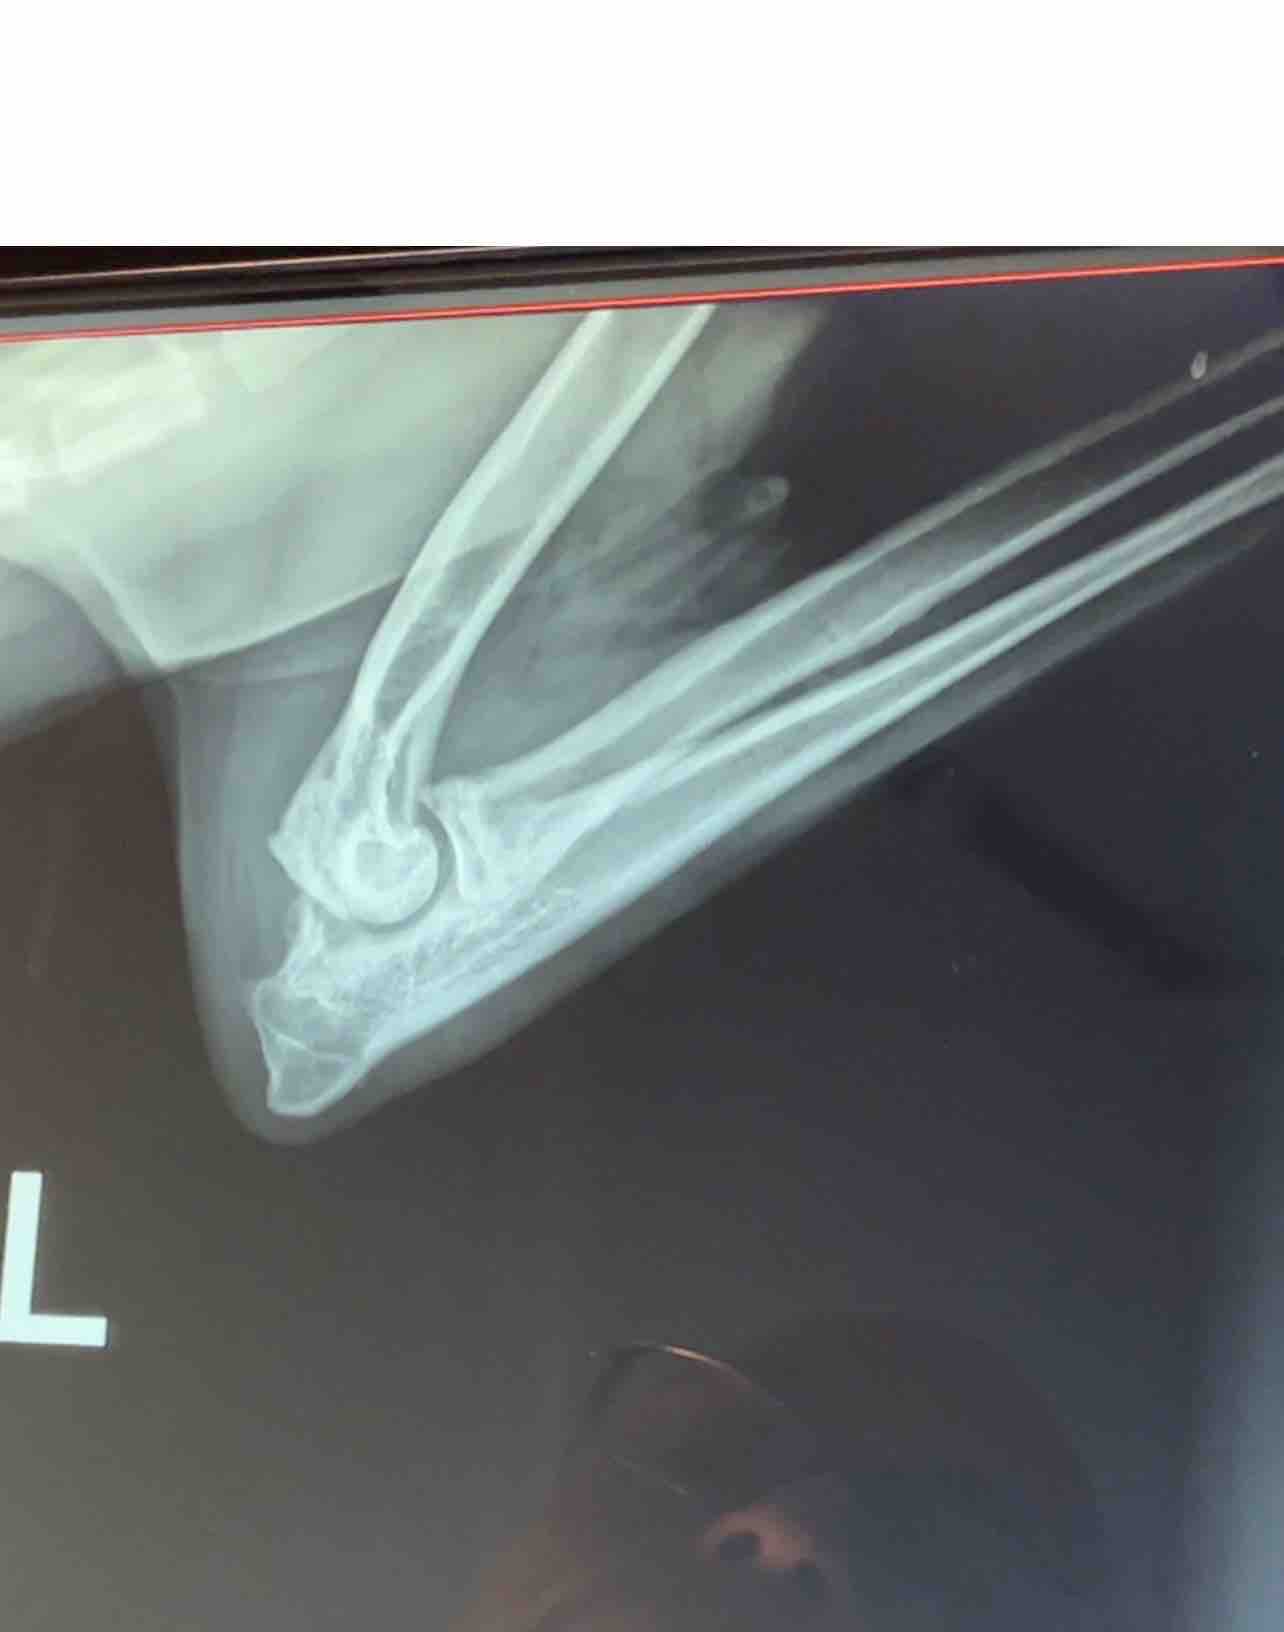

After X-rays, our vet diagnosed Tucker with elbow dysplasia, a condition where the elbow joint does not develop properly. It causes pain and limits mobility. While it cannot be cured, it can be treated.

Tucker now needs orthopedic surgery on his front left leg. There is also concern that a bone fragment may have broken off because of this condition. While we are hopeful surgery will fix this, amputation is a possibility.